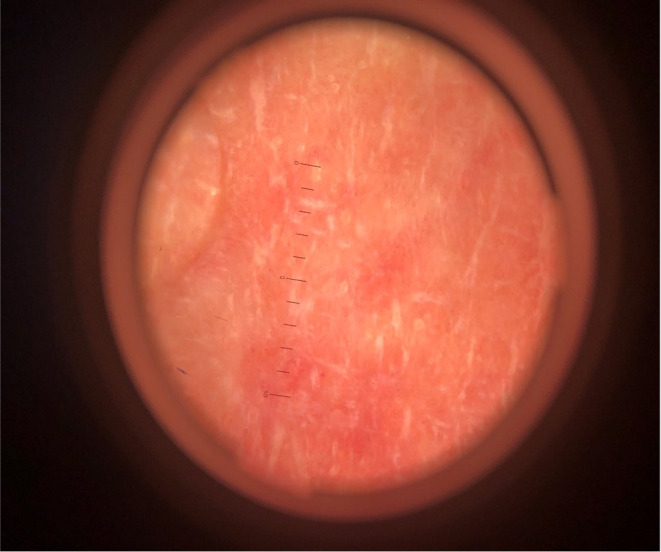

Hand transplantation is a vascularized type of composite tissue allotransplantation (CTA), involving the transfer of heterogeneous tissues such as skin, fat, bones, muscles, and nerves. Even with modern immunosuppression protocols, rejection remains a major obstacle in this field. We report the first documented case of eczema limited to the skin of a transplanted hand in a 38-year-old male born without a left hand. The patient underwent hand allotransplantation in December 2016 from a deceased donor with complete HLA mismatch and remained on stable triple immunosuppressive therapy. Six years post-transplantation, erythematous macules, papules, scaling, and increased keratosis appeared exclusively on the dorsal and palmar aspects of the grafted hand, involving approximately 80% of its skin surface, without lesions elsewhere. Histopathological examination confirmed subacute eczema, with no signs of acute or chronic rejection. Topical mometasone furoate ointment combined with an increased dose of oral prednisone (from 5 mg/day to 10 mg/day) resulted in marked improvement within two weeks, followed by complete resolution after several weeks of regular emollient use. No recurrence was observed during six months of follow-up. This case highlights the importance of differentiating between rejection and other dermatological conditions, such as eczema, in limb transplant recipients. Because eczema can closely mimic rejection, it may complicate post-transplant care and lead to unnecessary changes in immunosuppressive therapy if misdiagnosed. Accurate diagnosis is essential for appropriate management and graft survival.